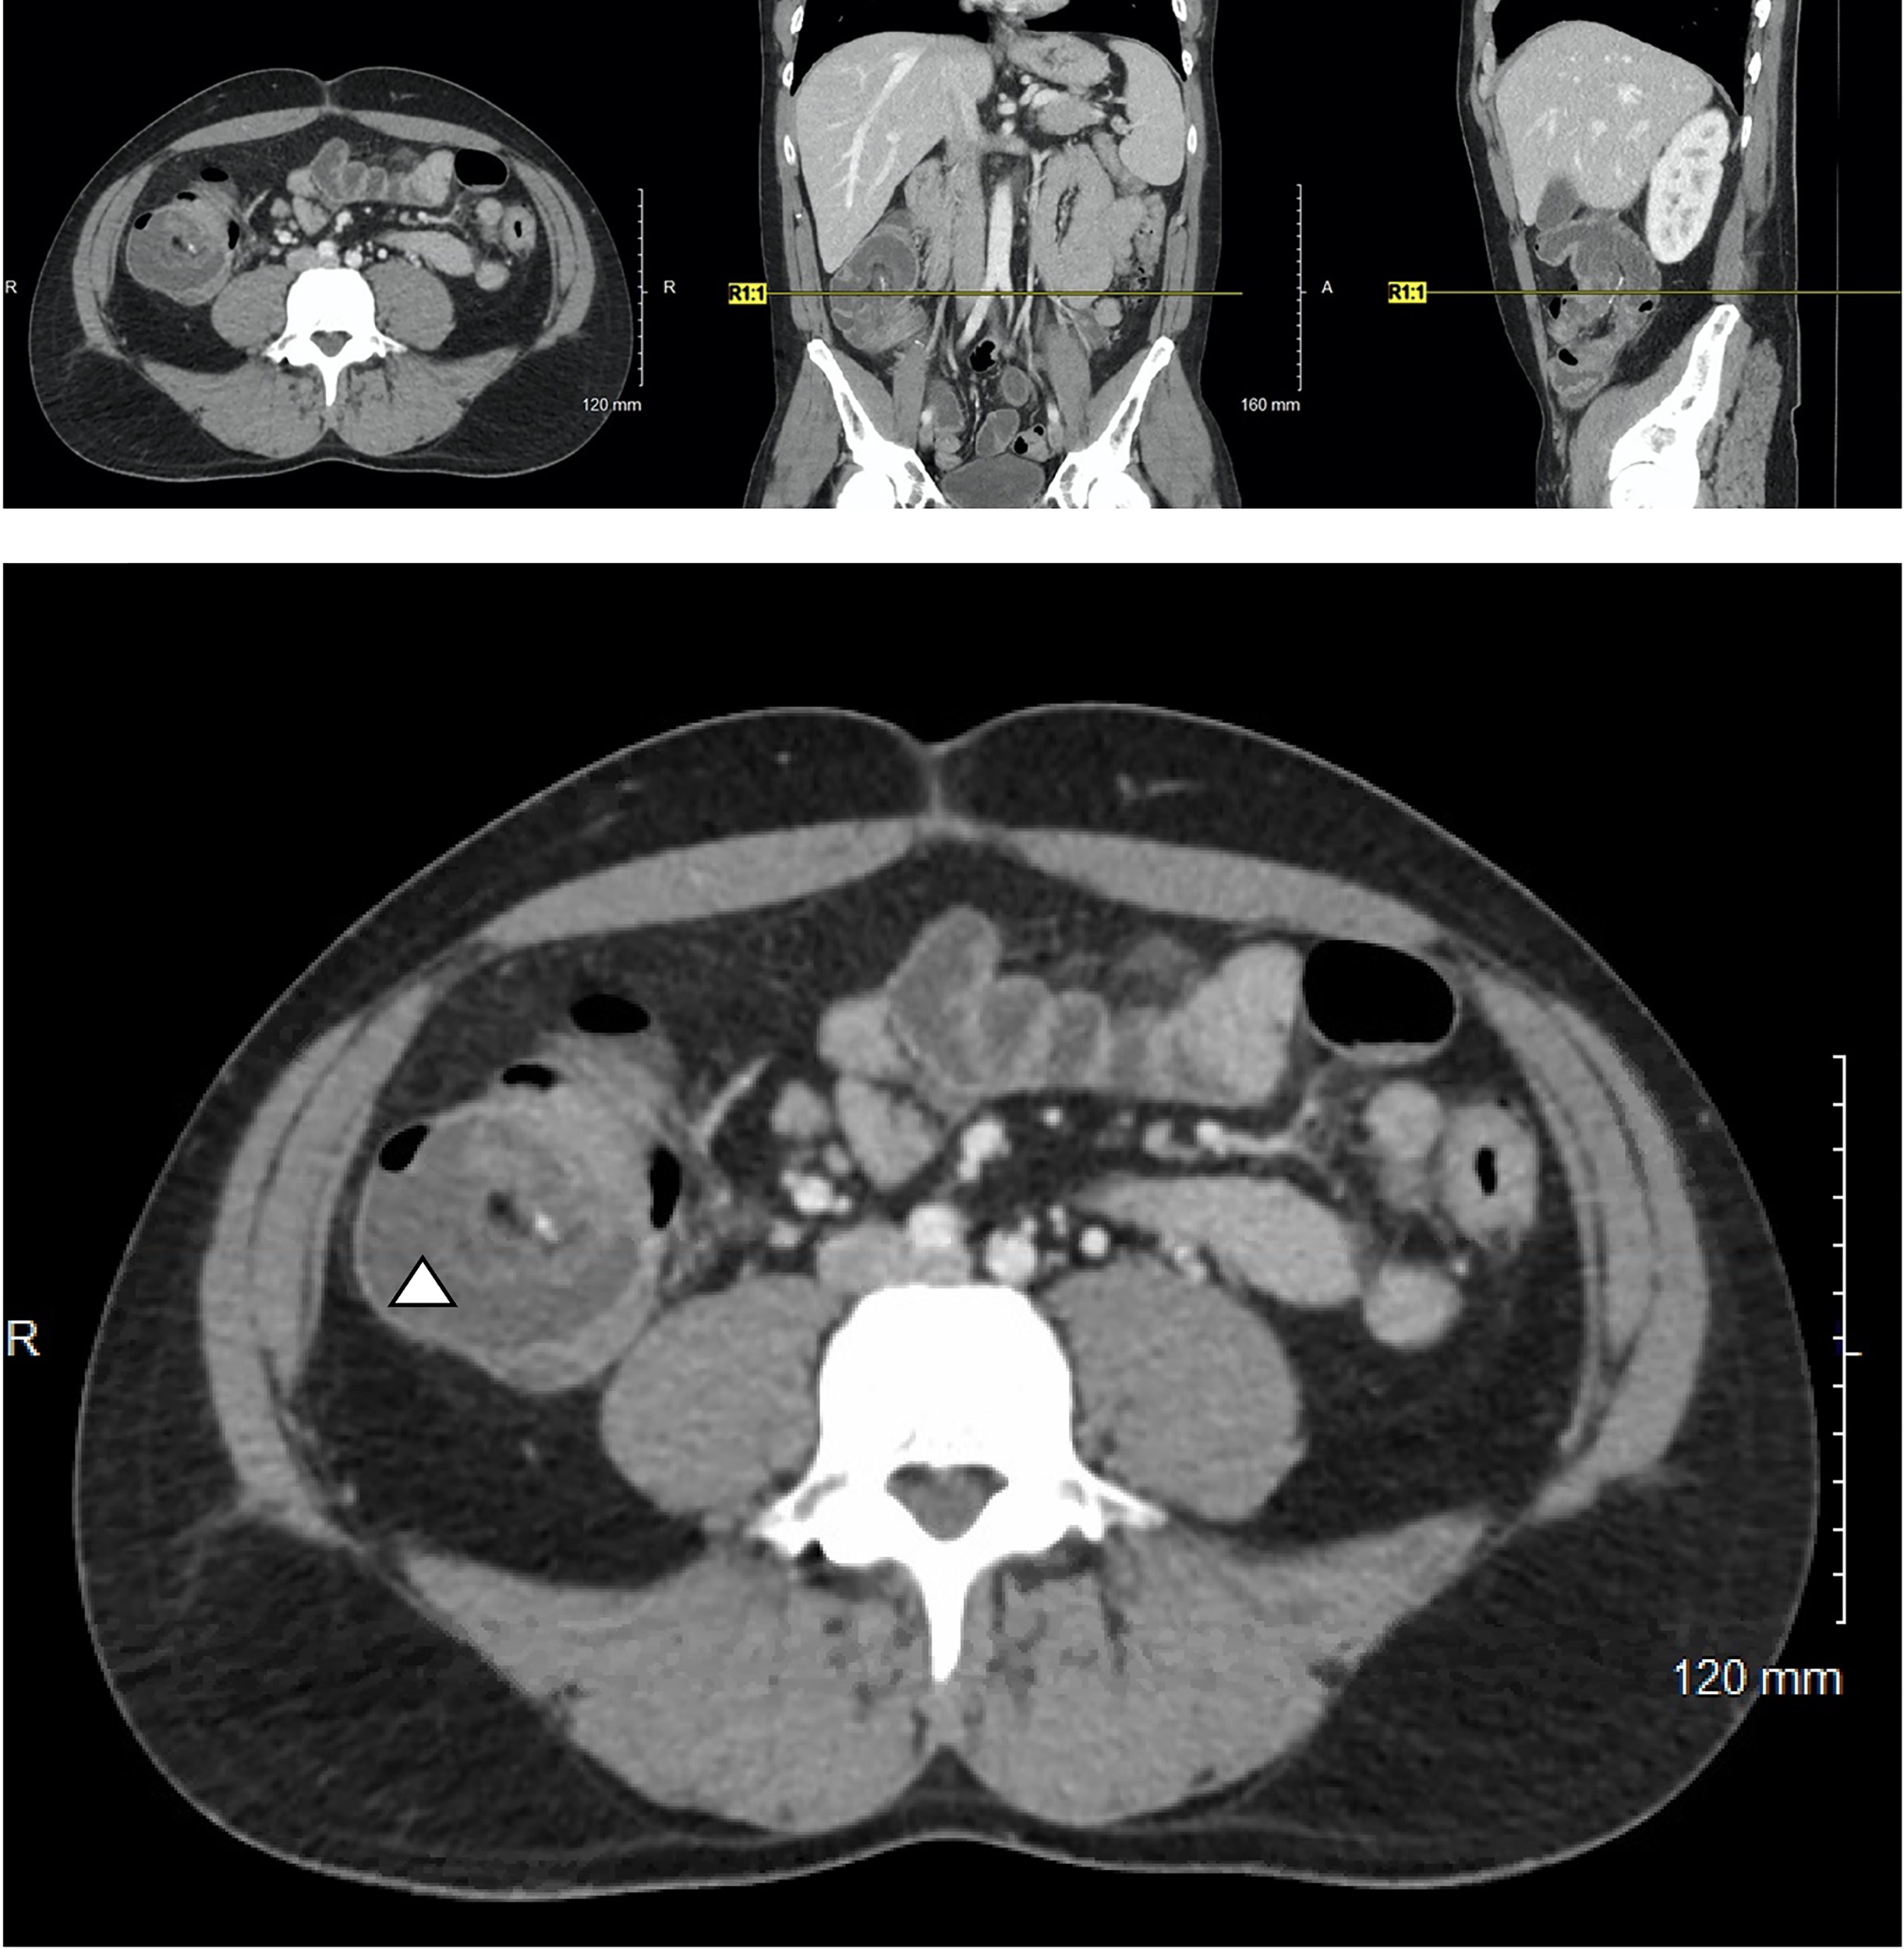

Soon thereafter, he presented to the emergency department with 24 hours of fatigue, weakness, peritoneal abdominal pain, and diarrhea that progressed to bright red blood per rectum. Cross-sectional imaging at the time demonstrated ileocecal intussusception and raised concerns for a cecal mass (Figure 2) suggesting neoplastic disease. Due to peritonitis, he was taken to the operating room and underwent an exploratory laparotomy. Intraoperative findings identified significant cecal induration, marked inflammation, patchy areas of ischemia, and the appearance of cecal intussusception. Specifically, the cecum appeared to invaginate from the coalescence of the tinea (where the appendiceal orifice would have been; however, the patient had a laparoscopic appendectomy years prior) and had intussuscepted antegrade along the ascending colon (Figure 3). There were signs of colonic ischemia, but no gangrene or perforation, and the affected area was resected with right hemicolectomy. Intestinal continuity was restored with an ileocolonic anastomosis. The postoperative course was complicated by a minor wound seroma and colitis with diarrhea that resolved with conservative management. The final surgical pathology was consistent with localized colonic ischemia and necrosis due to intussusception, with surrounding colitis. No evidence of malignancy was identified, and 30 reactive lymph nodes were recovered without evidence of metastasis. Notably, the lead point for the intussusception appeared to be at the site of the appendiceal stump from his prior appendectomy. At the time of manuscript preparation, the patient is doing well having completed encorafenib and binimetinib treatments and has had no further evidence of disease recurrence.

Figure 2

Cross-sectional imaging of a 37-year-old M with Stage IV in-transit melanoma receiving immune checkpoint inhibitor therapy who presents with severe abdominal pain. A characteristic target-sign for intussusception is appreciated in cecum (triangle) and can be seen on the axial, coronal, and sagittal views.